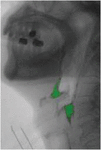

images

Figure 6 Experimental results of barium extraction based on background subtraction.

Figure 7 Enlarged display of experimental results.

However different lighting conditions will lead to VFSS video image research, therefore, we need from a frame to use gaussian background model of gray image algorithm to adjust balance in the appeal of models, we the pixels by weighted gaussian mixture distribution model, results show that fluid of VFSS barium extraction has a certain impact. The picture shows the result. The background subtraction algorithm greatly improved the effect of body part shaking, and the accuracy of barium extraction was up to 85% (relative to the expert mark), which was significantly better than the results obtained by the frame difference algorithm alone, but the overall calculation time was improved.